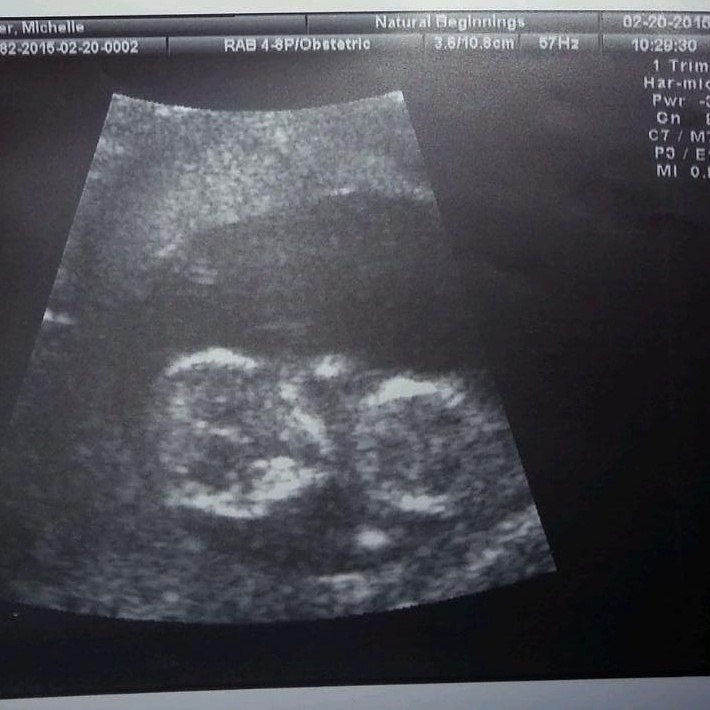

I got one at 7w and then today at 12w.(surprise extra u/s since the doppler couldn't pick up the heartrate!) Our little baby has grown a lot in 5 weeks!